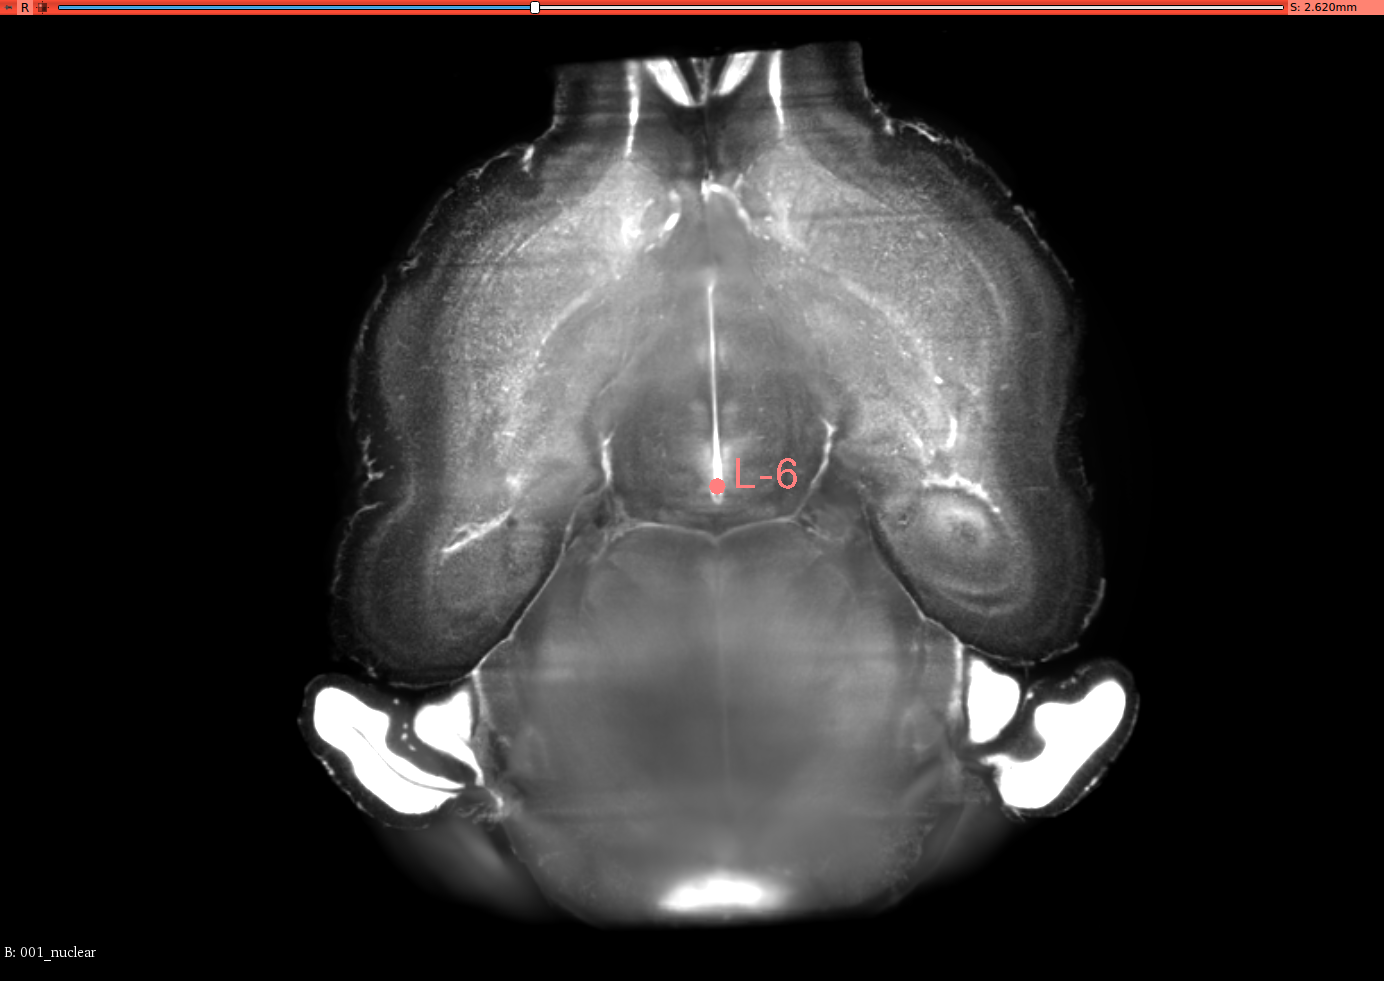

To validate the registration performance of the proposed methods and comparing the baseline methods in a more objective manner, a landmark registration test is conducted. In the CUBIC dataset, three brains are used to test the registration performance. In the landmark test, the same dataset is used for the performance validation. 12 landmarks are selected and all of these landmarks are selected where their positions vary in all three axis. 3D slicer tool is used to select the landmarks for this experiment from the CUBIC brains. A set of selected landmarks are shown in Figure 7. Table 3 shows the results of the 3D landmark registration by proposed InvGAN method and other baseline methods. The Euclidean distance between the registered landmarks and reference landmarks are presented in mm. For optimisation-based ANTS and Elastix tools, the same parameter sets are used to register landmarks selected from moving image and fixed image. After the registration, the output point locations are compared with reference point locations in the fixed image. For the deep-learning-based VoxelMorph and InvGAN, the deformation values in X,Y and Z are extracted from the same voxel location of the selected landmark’s voxel location. After applying deformation to the landmarks, the new position is compared with that of corresponding reference points in the fixed image.

Refer to caption

(a) Brain-1

(b) Segittal View

(c) Coronal View

(d) Corresponding Points in Brain003

(e) Segittal View

(f) Coronal View

(g) Brain-2

(h) Segittal View

(i) Coronal View

(j) Corresponding Points in Brain-3

(k) Segittal View

(l) Coronal View

Figure 7: 3D Landmarks